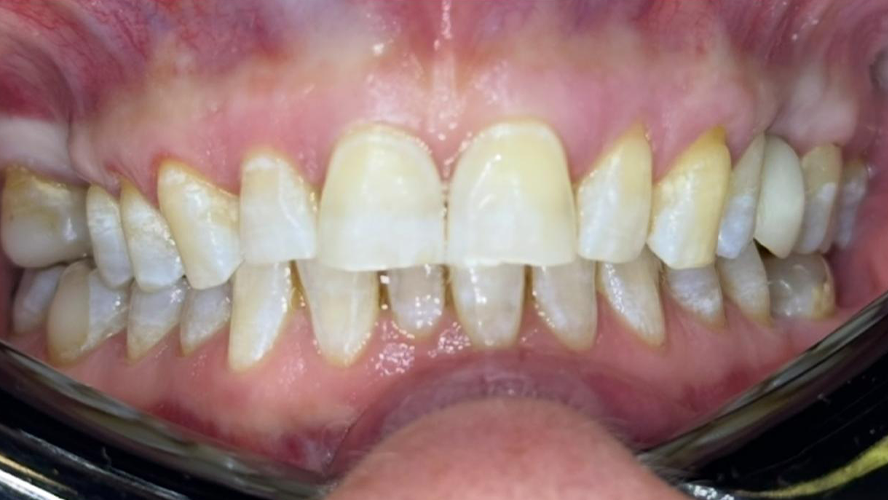

Kompleksowa odbudowa zgryzu

Kompleksowa odbudowa zgryzu łącząca leczenie ortodontyczne, fizjoterapeutyczne, implantologiczne oraz protetyczne pod postacią koron i licówek ceramicznych.